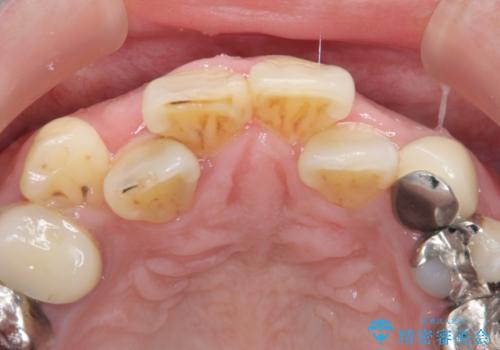

また、左上の犬歯の根の再治療も行いました。

- ジルコニアクラウンスタンダード・仮歯 13.2万円×6 左上3精密根管治療(リトリートメント)・ファイバーコア 12.1万円費用は治療当時の料金となります

最終的な被せ物は抜歯を行なってから半年経ってから形を整えて型取りを行います。